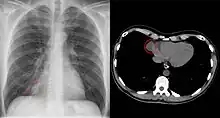

Small pericardial cyst circled on chest x-ray (left) and chest CT scan (right).

Since pericardial cysts are often asymptomatic, the most common diagnosis is through incidental finding on a chest x-ray.[1][2] Differentiation of pericardial cysts from diverticula is usually impossible as both the lesions have similar radiological appearance. The lone differentiating feature is the presence of communicating tract between pericardium and the cyst cavity in the diverticula, unlike the fully walled off pericardial cyst.[4][5] When patients have symptoms, transthoracic echocardiogram is one of the first tests used to look for a pericardial cyst.[3] CT or MRI may also be used to diagnose pericardial cysts.[4][6][7] On CT and MRI a pericardial cyst will commonly appear as a round, fluid-filled structure surrounded by thin walls.[4][6][7] Diagnosis of a pericardial cyst can also be made before birth using ultrasound.[2]